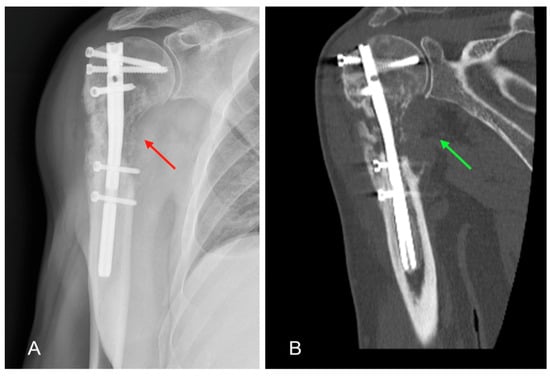

Given the suspicion of a neoplastic lesion, it was decided to carry out an in-depth diagnostic with an MRI examination to complete the local instrumental imaging which highlighted a subversion of a voluminous portion of tissue in the proximal III of the humerus with manifestation in the periskeletal soft tissues, compatible with a replacement lesion (Figure 3). S CT-guided biopsy was performed to realise histological examination.

Figure 3. MRI scans of the left arm showing intramedullary nail (red arrow) and periskeletal neoplastic pathological tissue (green arrows) at the level of the humeral head and diaphysis: (A) coronal MRI section; (B) transversal MRI section.